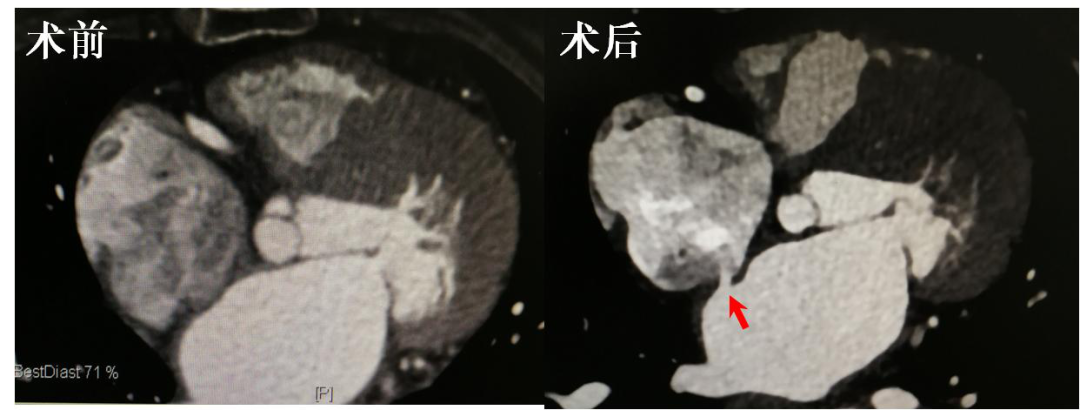

图解:术前患者房间隔完整,术后房间隔制作出一边缘清晰的瘘口(红色箭头所示),其前后径约5mm。